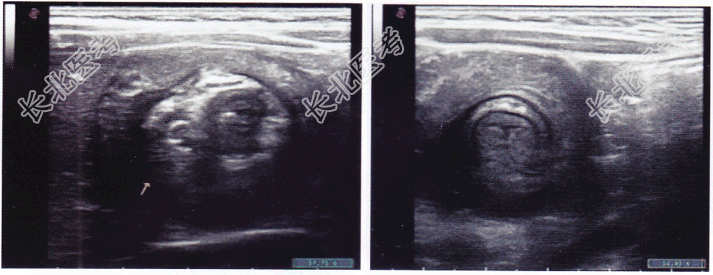

- 单项选择题患儿,男性, 2岁,突发腹痛, 哭闹不止就诊,超声所见如图所示, 以下最可能的诊断是

A、肠道蛔虫

B、肠套叠

C、肠道占位性病变

D、急性阑尾炎

E、以上都不对